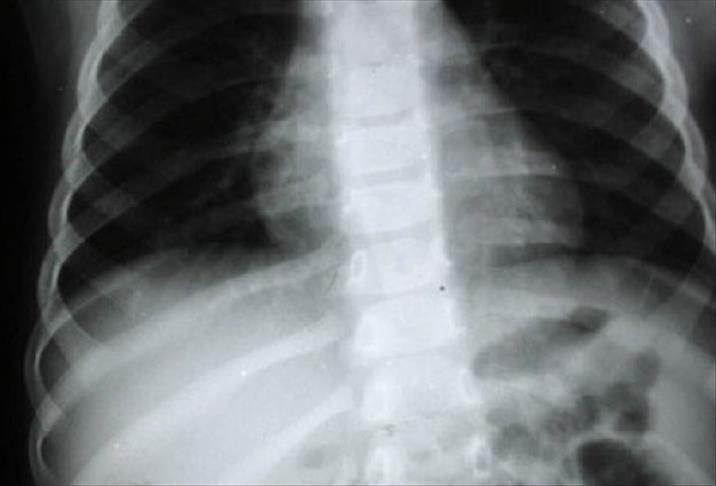

BİRİNCİL, İKİNCİR KANSER

Hızla yayılan agrasif bir kanser türü olan akciğer kanseri, akciğerde oluştuğunda birincil, başka organlarda oluşup akciğere sıçradığında ikincil kanser adını alıyor.